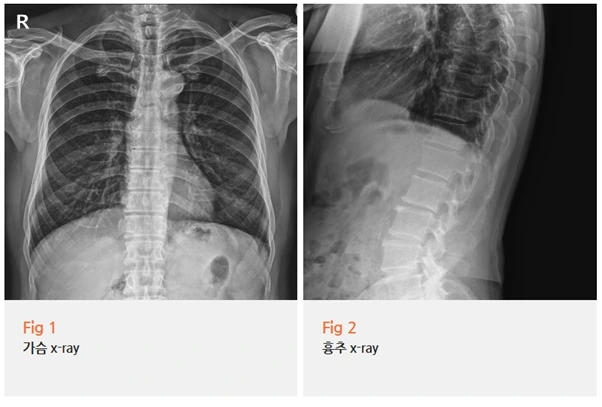

내과에 가셔서 심전도, 심장 초음파,

흉부 X-ray까지 다 찍어보셨는데...

결과는 "아무 이상 없습니다"였다고 하시더라고요.

저희 콕병원에서 이 환자분을 진료할 때는

X-ray 검사와 기본 검사를 진행했어요.